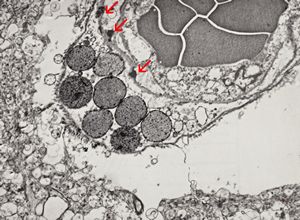

M,71y. | CADASIL accompanied with Alzheimer disease - brain vessel - arrows: granular osmiophilic material (GOM) between basement membranes

M,71y. | CADASIL accompanied with Alzheimer disease - brain vessel - arrows: granular osmiophilic material (GOM) between basement membranes

M,71y. | CADASIL accompanied with Alzheimer disease - brain vessel - arrow: granular osmiophilic material (GOM) in basement membrane